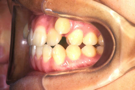

治療前

治療後

小臼歯は抜歯せずに、知歯を抜歯して治療しました。

①主訴 八重歯 ②診断名 叢生 ③年齢 17歳 ④使用装置 エッジワイズ装置 ⑤抜歯部位 下あご左右知歯 ⑥治療期間 約1年半 ⑦治療費概算 90万円